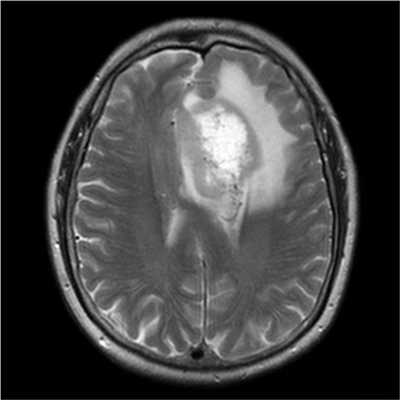

Злокачественные опухоли характеризуются инвазивностью, то есть врастанием в здоровые ткани, поэтому контуры таких образований нечеткие и неровные, а потому достоверно определять границы таких опухолей довольно сложно. Кроме того, структура злокачественной опухоли часто бывает неоднородна за счет распада (некроза), кровоизлияния и коллоидной дегенерации. Вокруг злокачественной опухоли, как правило, выявляется выраженный перифокальный отек, который может приводить к смещению срединных структур головного мозга и появлению аксиальной дислокации. Также могут быть выявлены признаки метастазирования.

Как выглядят метастазы на МРТ

Видны ли метастазы на МРТ, зависит от их размеров: МР-изображения показывают очаги более 1,5-2 мм, меньшие отсевы опухоли обнаруживает ПЭТ-КТ.

На снимках метастазы выглядят, как очаговые неоднородные образования, единичные или множественные, с тенденцией к слиянию, может присутствовать зона некротизации. Пораженный лимфатический узел чаще округлой формы, увеличен в размерах. Для лучшей визуализации используют контрастное вещество на основе солей гадолиния.